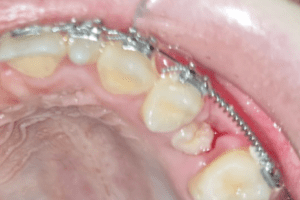

Foto ortopanoramica: possiamo osservare il 25 (secondo premolare di sinistra), che non ha sufficiente spazio per erompere, perché bloccato dal 24 (primo premolare di sinistra) e dal 26 (primo molare di sinistra)

Dopo un’attenta analisi radiografica, abbiamo optato per un trattamento ortodontico che ci ha permesso, grazie ad una molla, di creare lo spazio sufficiente per l’eruzione del 25